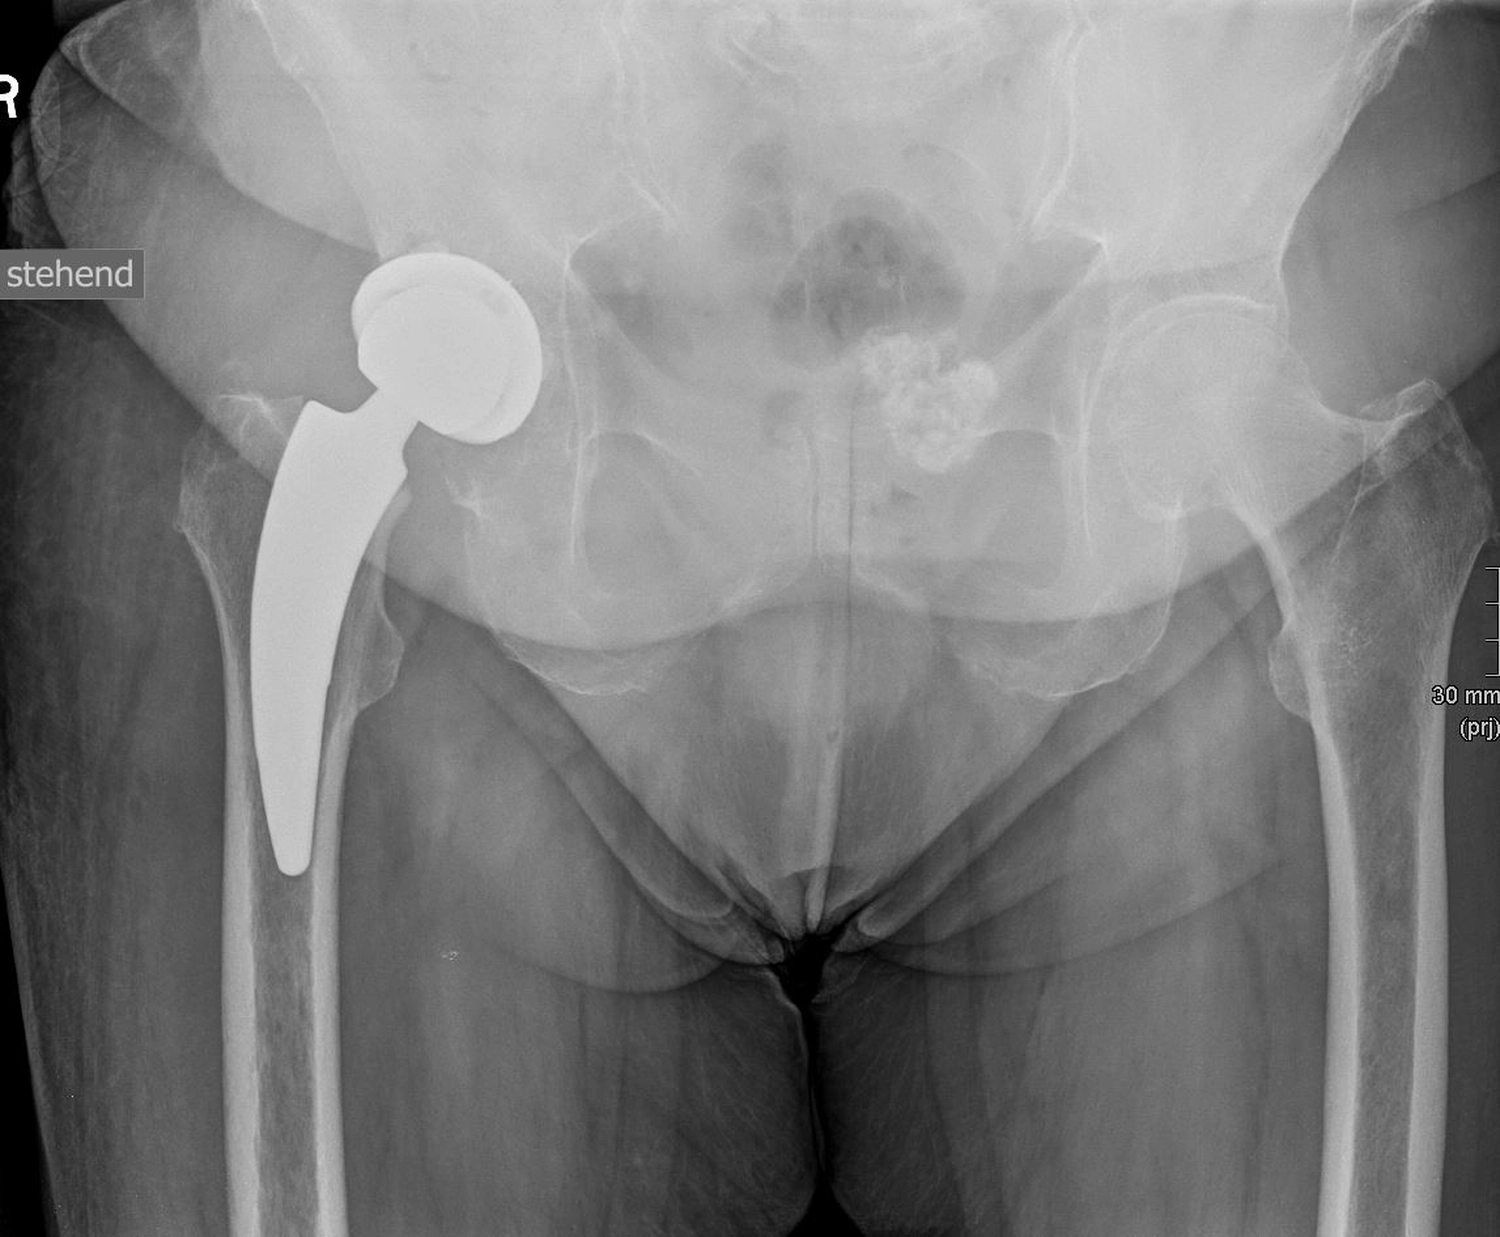

Ein künstliches Hüftgelenk ersetzt die geschädigten Teile des natürlichen Gelenkes. Es besteht aus mehreren Komponenten, die gemeinsam ein neues, stabiles und bewegliches Gelenk bilden. Die Pfanne wird in das Becken eingesetzt. Der Schaft wird im Oberschenkelknochen verankert. Der Prothesenkopf sitzt oben auf dem Schaft und bildet die „Kugel“ des Gelenkes und bewegt sich reibungsarm in der Pfanne.

Je nach Knochenqualität und Alter der PatientInnen werden zwei Verfahren angewendet.

Bei der zementfreien Prothese werden der Schaft und die Pfanne fest eingepresst und eingeschlagen. Der Knochen wächst in die aufgeraute Oberfläche ein und fixiert die Prothese dauerhaft.

Bei der zementierten Prothese werden die Prothesenteile mit einem speziellen Knochenzement befestigt. Der Vorteil besteht in einer sofortigen Stabilität, besonders geeignet bei älteren oder osteoporotischen PatientInnen.

Daneben gibt es sog. Hybridverankerungen, z. B. Pfanne zementfrei, Schaft zementiert.

Moderne Prothesen, wie wir sie hier in Stenum verwenden, sind so konstruiert, dass sie reibungslos, stabil und langlebig funktionieren, meist über viele Jahre bzw. Jahrzehnte (15–20 Jahre).

Dank der modernen Materialien und gewebeschonenden Techniken des Einbringens, (minimalinvasiver Zugang) ist die Hüft-TEP heute ein sehr erfolgreicher Eingriff, der vielen Menschen eine deutliche Verbesserung ihrer Lebensqualität ermöglicht.